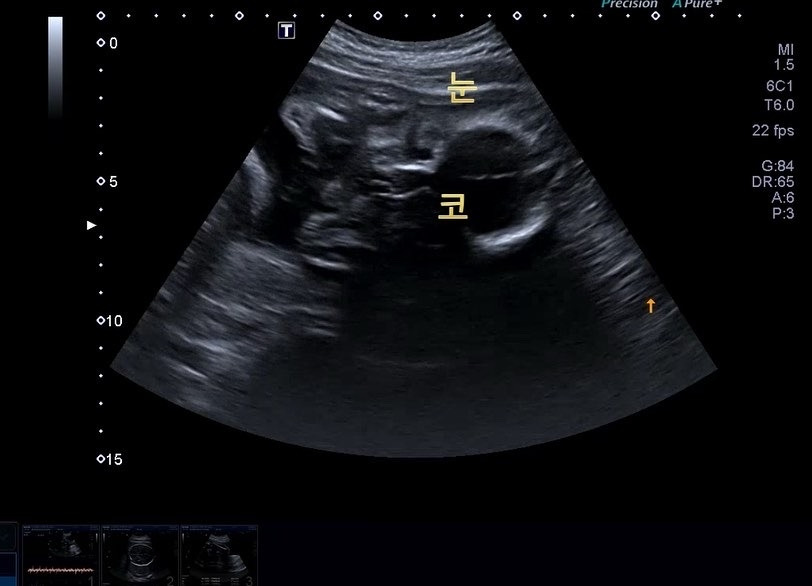

다올이 얼굴(눈+코)

29주 얼굴 눈 코.jpg

선생님이 말씀해주지 않으면 사실 구별이 어렵지만,

확실히 예전보다는 어디 어디 부분인지 파악을 하기 시작했다. 이제 엄마도 다올이가 익숙해졌나 봐